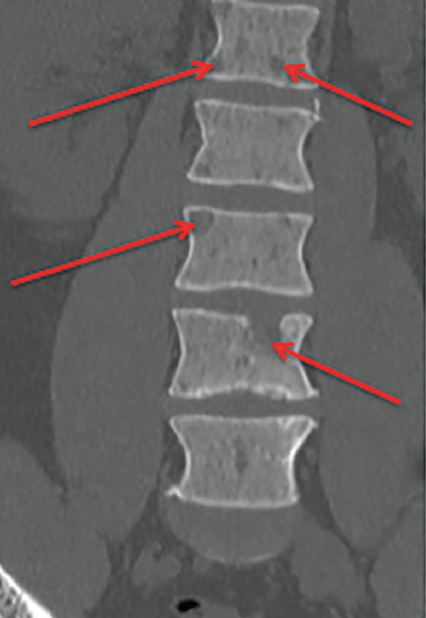

A 42-year-old African American man with no past medical history presented with isolated worsening back pain at the lumbosacral spine with no radiation for 6 to 7 months.

Sultan S. Ahmed, MD; Jasmin Ahmed, BS, MS, MD; Nicholas V. Mendez, BS; Kelsey A. Musgrove, BS; Syed A.A. Rizvi, PhD, MBA